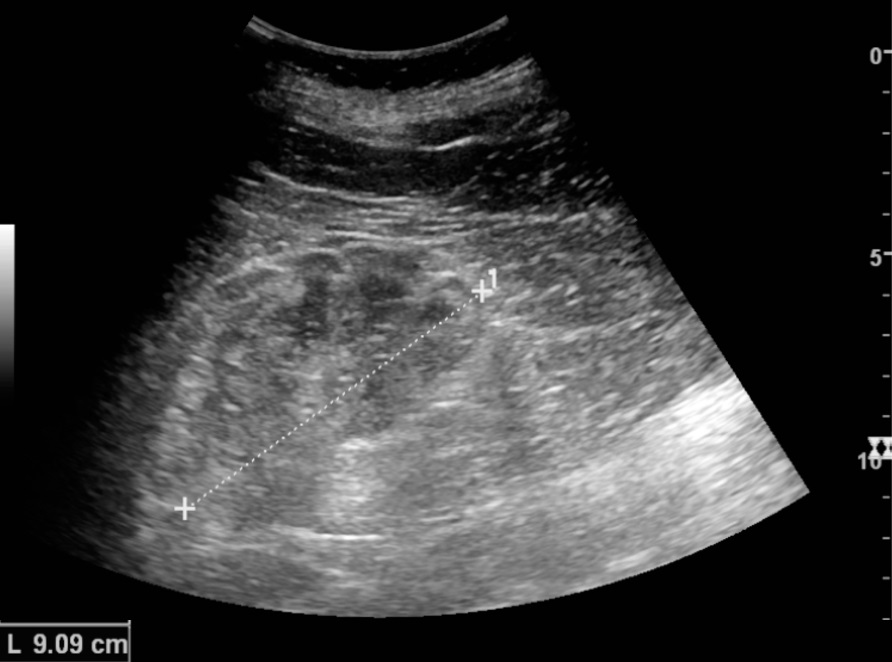

신장 초음파는 만성 신장 질환의 징후를 발견하는 데 유용하며, 이는 사구체신염 외에도 다른 많은 질환으로 인해 발생할 수 있다.[9] 신장 생검을 통해 병형을 확정한다. 신장 생검은 사구체신염의 종류와 중증도를 정확하게 판단하는 데 필수적이다. 면역형광 검사, 전자현미경 검사 등을 통해 진단한다.6. 치료